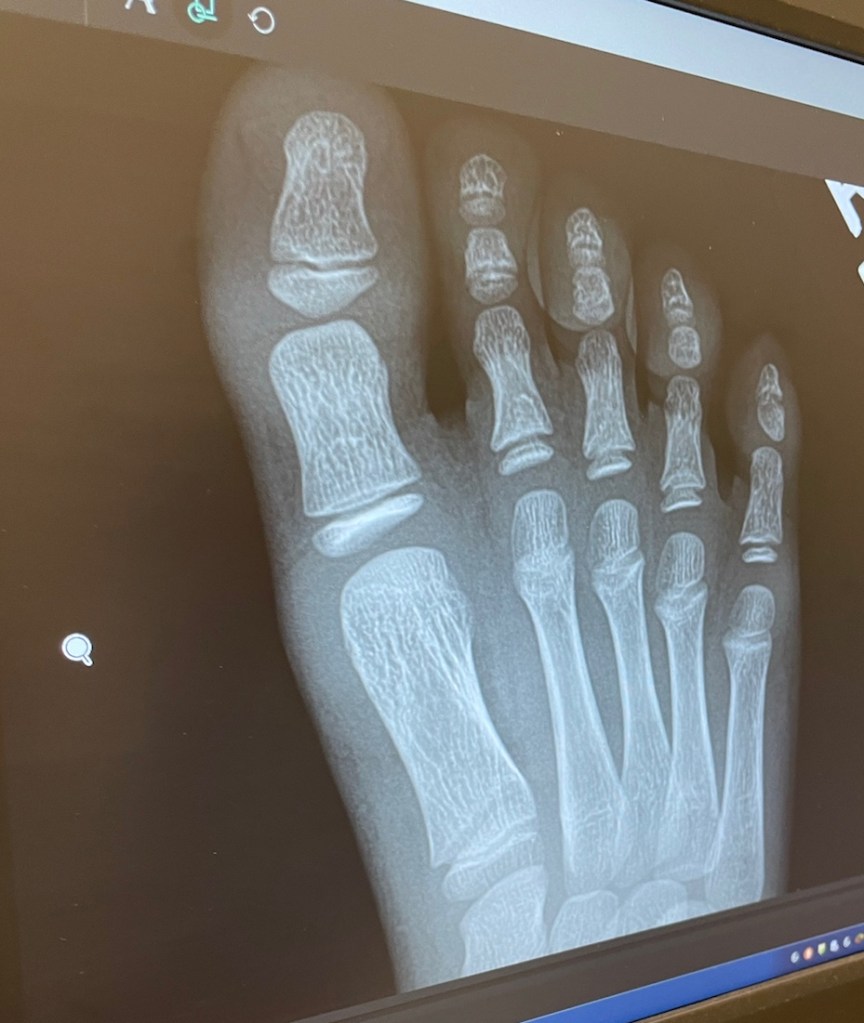

Morning in urgent care… at least there aren’t broken bones. April 7, 2021 R Nicely A heavy candle fell on his toe while horsing around with the little brother. Share this: Share on X (Opens in new window) X Share on Facebook (Opens in new window) Facebook Like Loading... Published by R Nicely View all posts by R Nicely